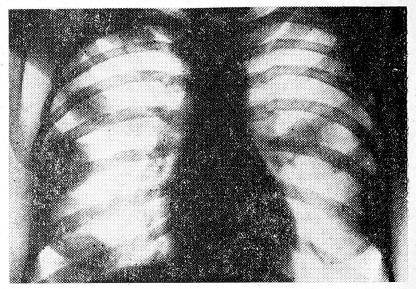

Раковый лимфангоит (11 больных) проявляется в виде тяжисто-сетчатой деформации сосудисто-интерстициального рисунка (рис. 4) преимущественно в средненижних отделах легких, симметрично с обеих сторон. Эта форма метастазов рака щитовидной железы встречается редко и является как бы предстадией мелкоузелковой диссеминации, когда в последующем на фоне сетчато-петлистого рисунка выявляются мелкие узелковые тени.

Рис. 4. Обзорная рентгенограмма легких Преимущественно в средне-нижних отделах легких раковый лимфангоит (метастазы рака щитовидной железы).